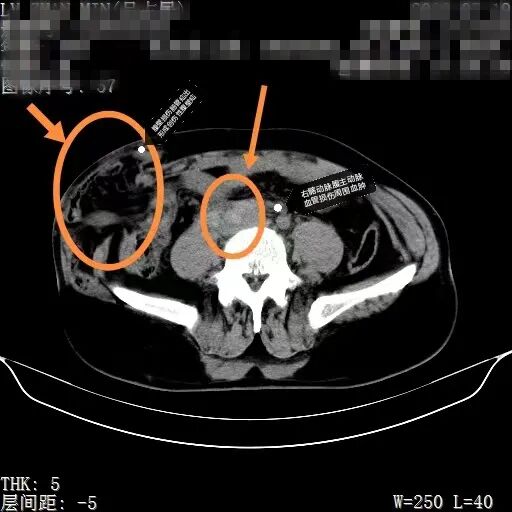

术前造影右髂总动脉与腹主动脉交界处血管壁损伤

来到市二院后,经过初步检查,吕先生被碾严重,肋骨骨折,腹壁肌肉断裂,肠管破裂,以及髋部、右臀部皮肤破裂受伤出血。CT检查中,还发现一个非常棘手的问题,右侧髂动脉与腹主动脉交界处有血肿,一旦破裂,就会有生命危险时间就是生命,普外一病区刘利亭主任当机立断,立即带领团队医护人员进入导管室,为吕先生实施侧髂动脉支架内隔绝术。在医护人员的不懈努力下,手术顺利完成。虽然拆掉了血肿这个最危险的“雷”,但吕先生的情况依然不容乐观。